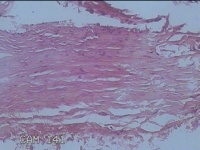

左侧臀部包块

性别

男

年龄

49岁

临床诊断

皮脂腺囊肿

一般病史

发现左侧臀部包块2年余,无明显疼痛及不适。

标本名称

大体所见

灰白暗红色组织2.5x2.3x1.3cm一块,便秘带梭形皮肤2.5x1.3cm,皮下见包块2.5x1.5x1.3cm一个,切开包块呈囊性,囊内充满大量灰白色角化物,囊壁厚0.1cm。

表皮样囊肿。

表皮样囊肿